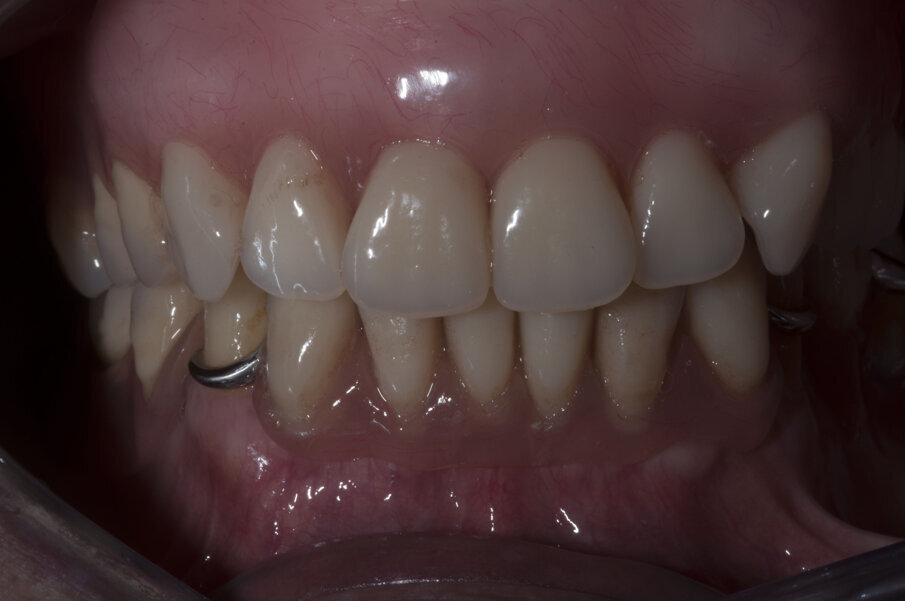

Verificata la precisione del lavoro si procede alla consegna. La Fig. 38 evidenzia la perfetta salute dei tessuti peri-implantari a protezione dei MUA, e nelle figure 39 e 40 evidenziano l’ottimo adattamento del manufatto finale ai tessuti intra ed extra-orali. La panoramica di controllo a 12 mesi dal completamento del lavoro evidenzia una perfetta stabilità dei livelli ossei dopo il carico protesico (Fig. 41).